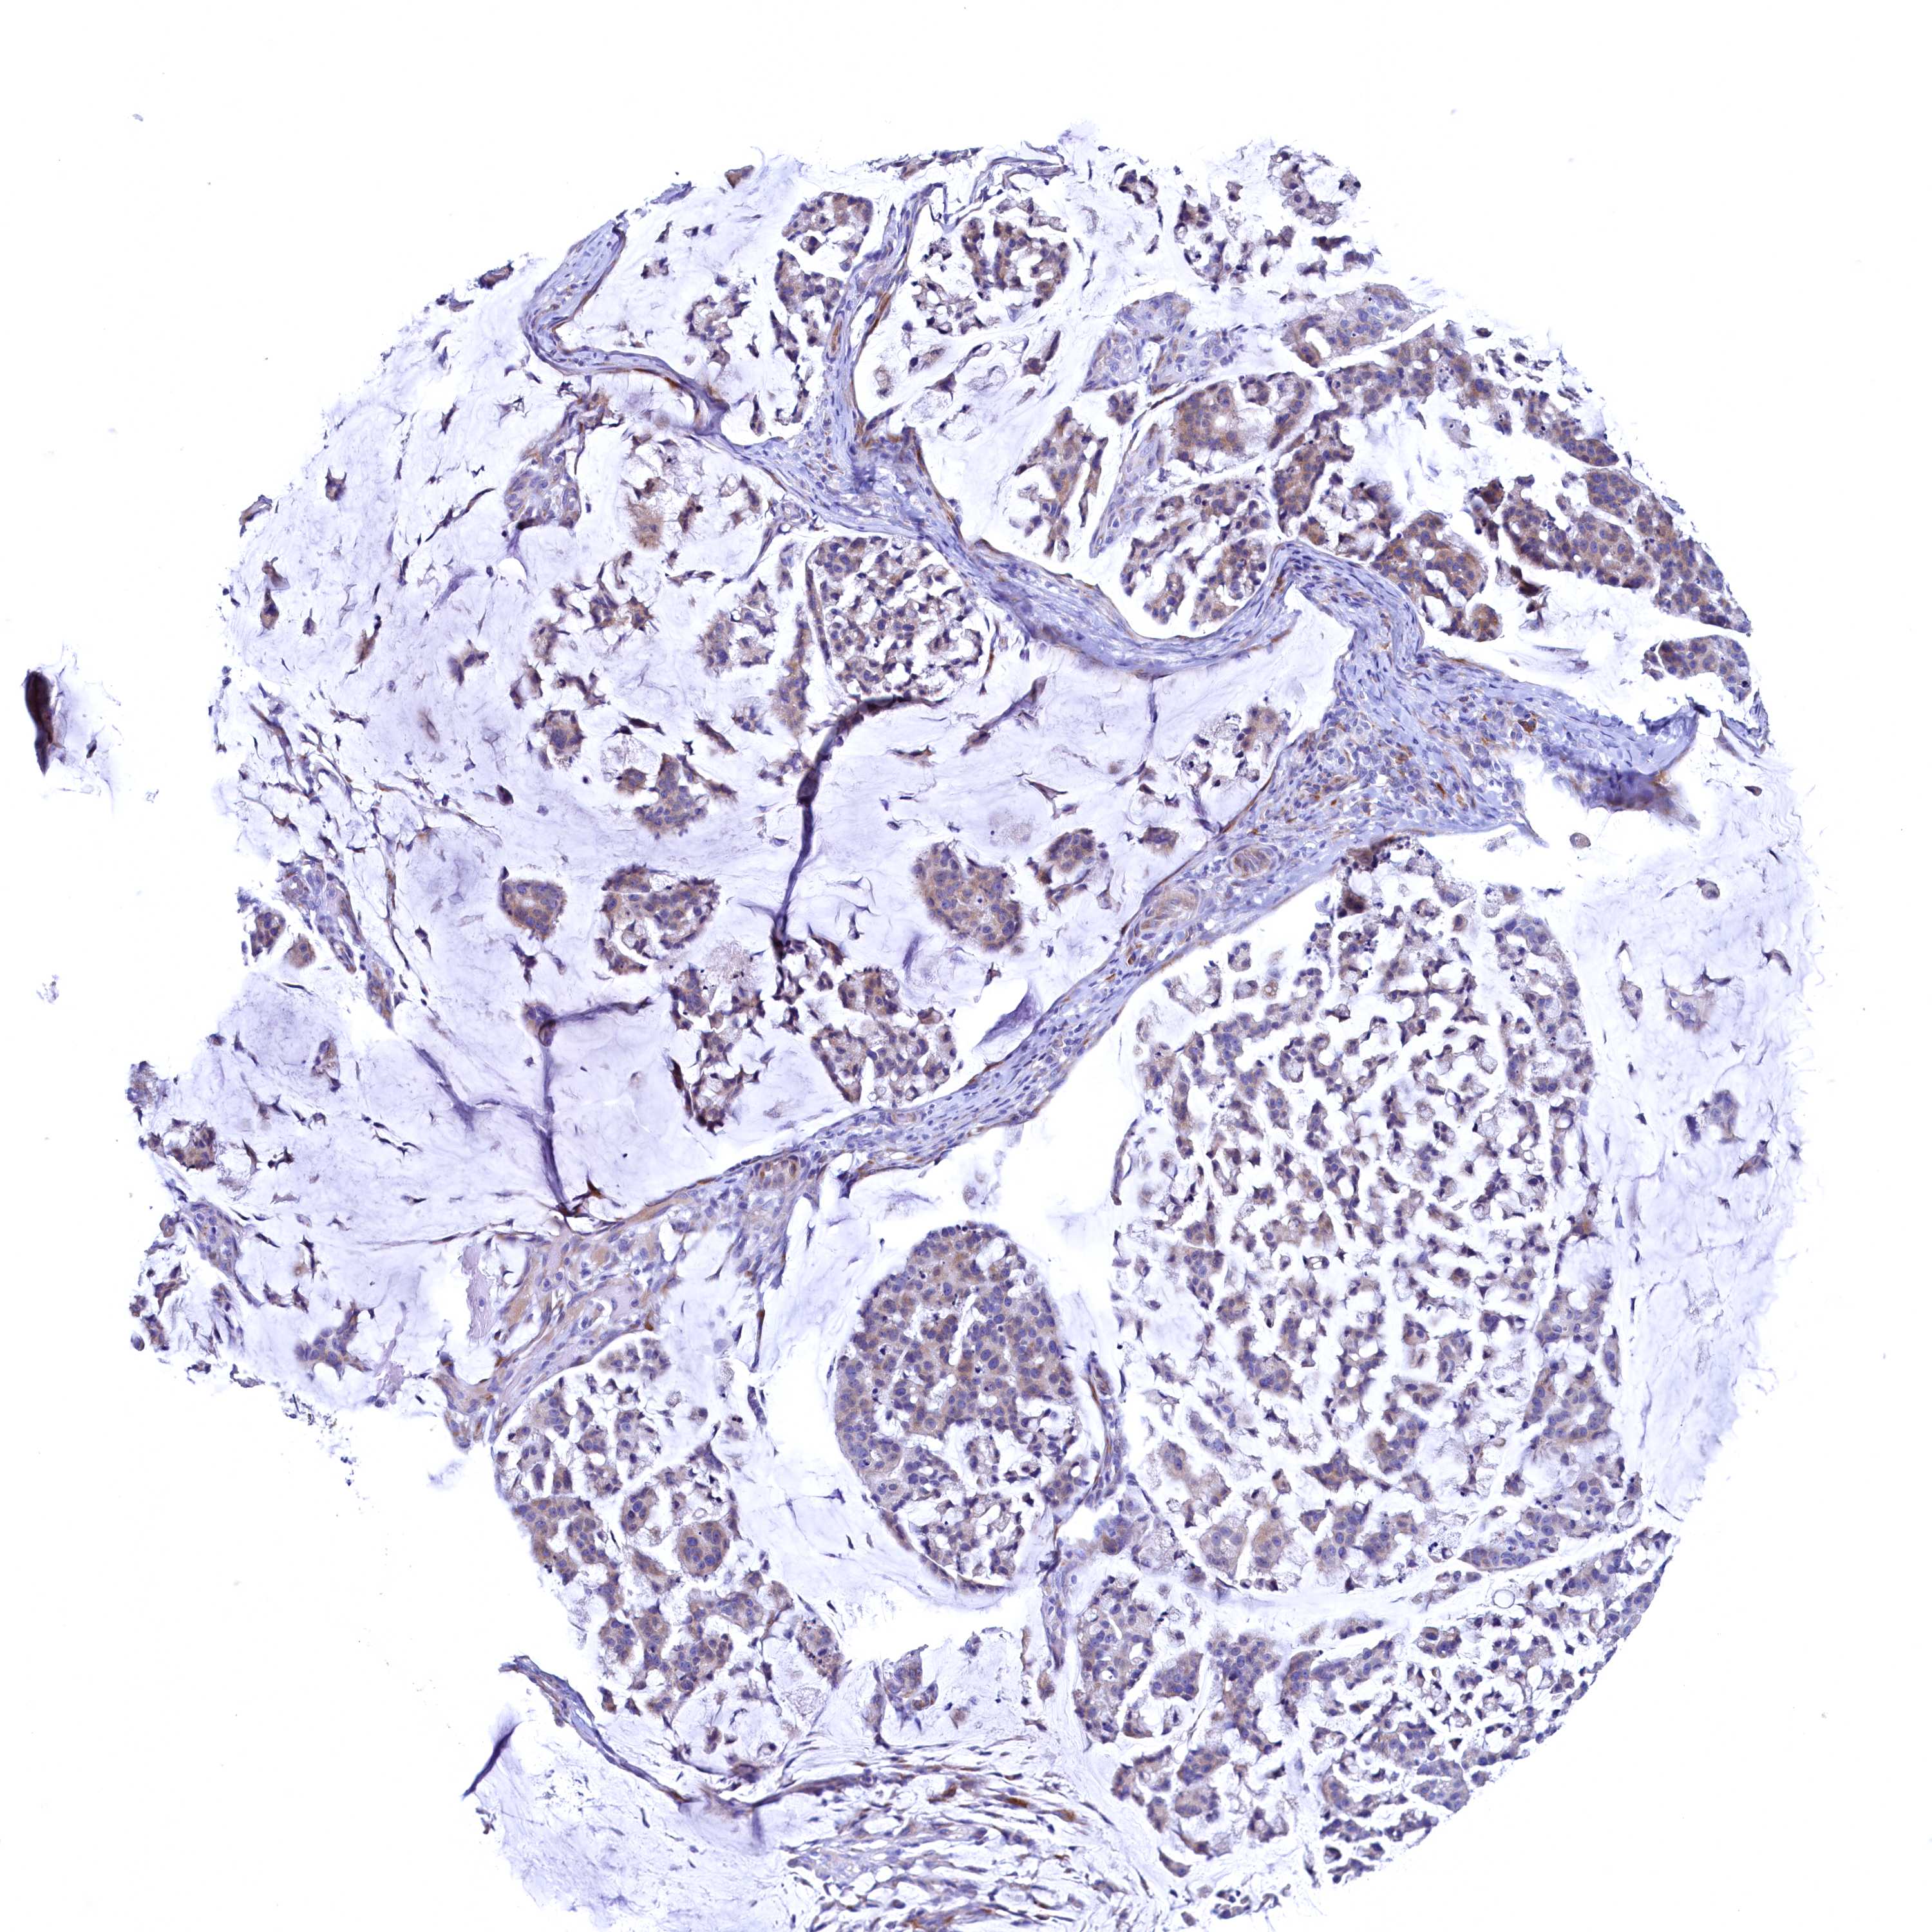

STOMACH CANCER - Protein expressioni

A mouse-over function shows sample information and annotation data. Click on an image to view it in a full screen mode. Samples can be filtered based on level of antibody staining by selecting one or several of the following categories: high, medium, low and not detected. The assay and annotation is described here.

Note that samples used for immunohistochemistry by the Human Protein Atlas do not correspond to samples in the TCGA dataset.

Antibody stainingi

Antibody staining in the annotated cell types in the current human tissue is reported as not detected, low, medium, or high, based on conventional immunohistochemistry profiling in selected tissues. This score is based on the combination of the staining intensity and fraction of stained cells.

Each image is clickable and will lead to virtual microscopy that enables deeper exploration of all samples and also displays staining intensity scores, fraction scores and subcellular localization as well as patient and tissue information for each sample.

Antibody HPA039908

Antibody HPA040774

Staining

High

Medium

Low

Not detected

Intensity

Strong

Moderate

Weak

Negative

Quantity

>75%

75%-25%

<25%

None

Location

Nuclear

Cytoplasmic/membranous

Cytoplasmic/membranous,nuclear

Adenocarcinoma, NOS

Adenocarcinoma, High grade